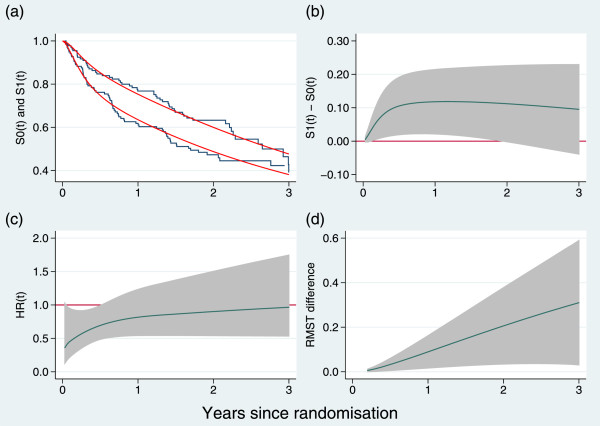

PATCH1 is a randomized, double-blind trial comparing a 12-month course of low-dose penicillin with a placebo in the prevention of recurrent cellulitis of the leg, a common baterial infection of the skin and underlying tissue [10]. The trial is rather small, with 129 events (patients experiencing one or more recurrences) among 274 patients followed up for a maximum of 3 years.

The results for PATCH1 are shown graphically in Figure 2 and in tabular form in Table 1 (we have omitted the equivalent of Table 2 since the results are indicated in Table 1 and Figure 2).

Figure 2.

Time-dependent outcome measures exemplified by the PATCH1 trial: (a) Kaplan- Meier curves (solid lines) and estimated survival functions (dashed lines) from a flexible parametric model; (b) difference in survival functions; (c) instantaneous hazard ratio; (d) difference in restricted mean survival time. Shaded areas are pointwise 95 intervals. Estimates in panels (b), (c) and (d) are derived from a flexible parametric model. Follow-up has been truncated at 3 years.

The results here are particularly intriguing. Neither of the individual treatment-effect tests are formally significant at the 5% level, although both are very close to significant (see Table 1). In contrast, the joint test has a P-value of 0.02. The conclusions from the trial analysis could hinge on which approach to testing was taken. Figure 2(c) shows that, as with GOG111, the treatment-effect HR appears substantial near t=0 and diminishes rapidly over the course of follow-up, being near 1 after 1 year. Note the generally large uncertainty in the estimates.